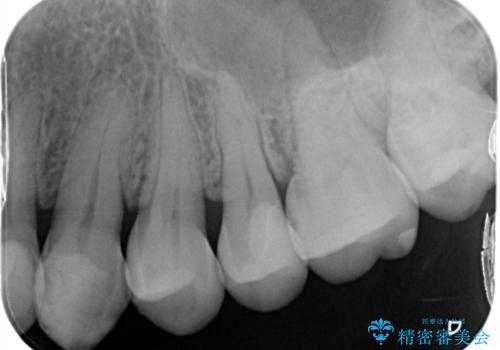

矯正後セラミックインレーにしたい

- 銀歯が気になるためやり替えたいとのことで来院されました。

セラミックインレーで治療を行いました。

口の中にチラつく銀歯は適合の良いセラミックインレーでやり替えることで綺麗にやり替えることができます。